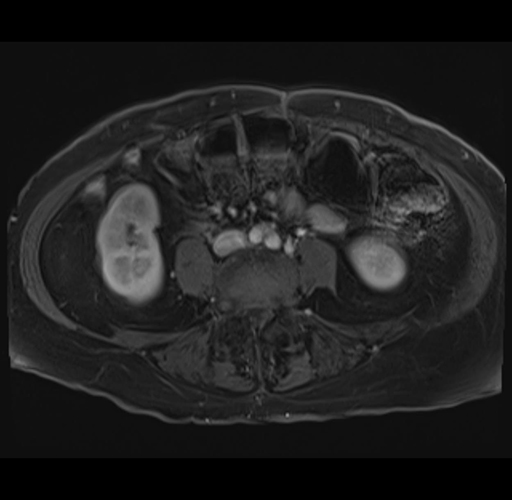

MRI T1

Imaging analysis